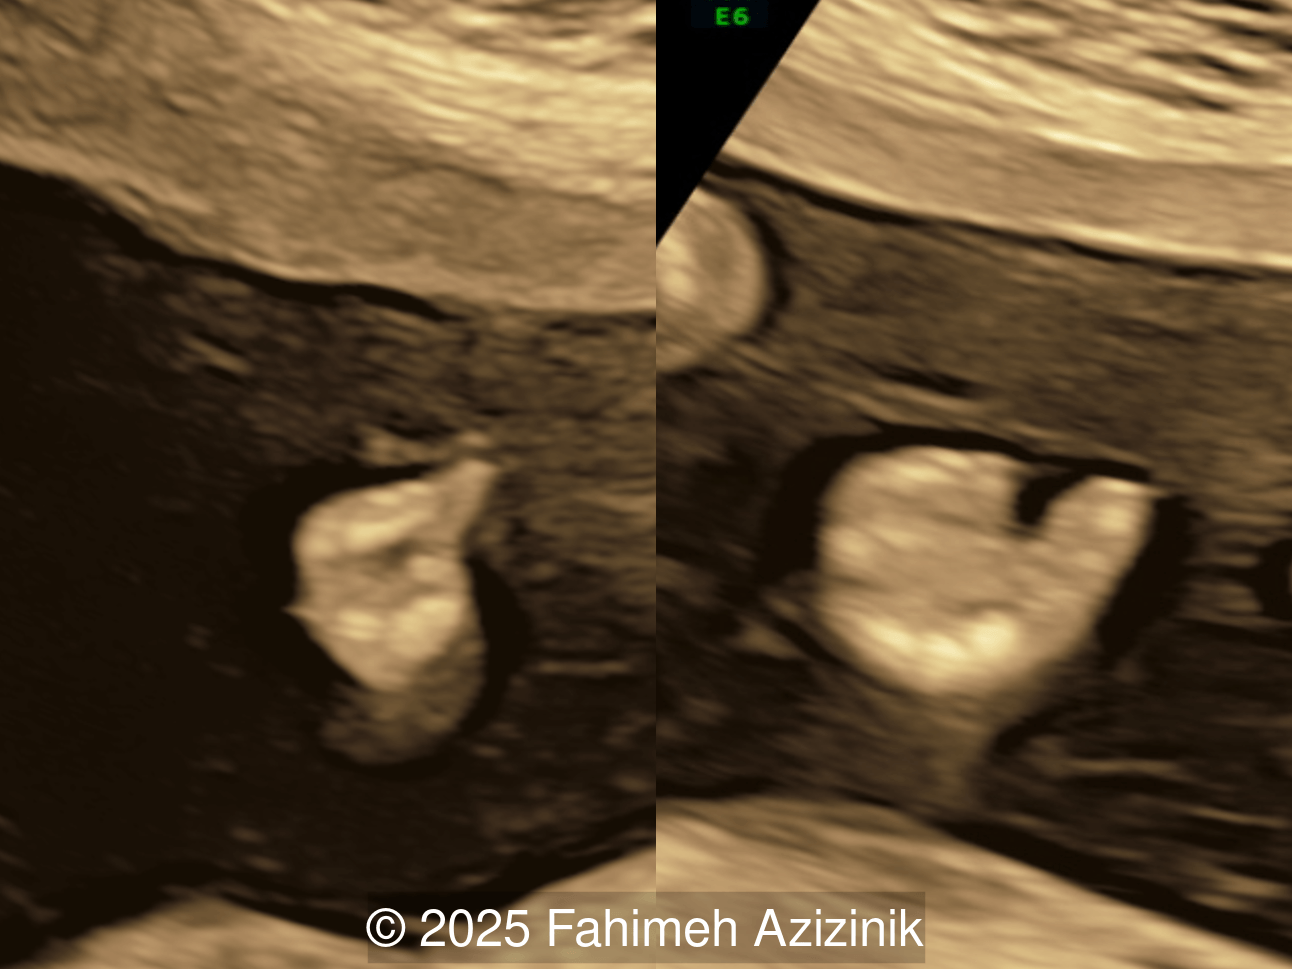

Image 2

• Complex syndactyly of the hands and feet. Complex hand brachysyndactyly with “mitten-like” appearance due to bony fusion of the fingers

Bicoronal synostosis is the characteristic cranial hallmark of Apert syndrome, detectable sonographically from 18 weeks. Its most recognizable manifestation is turribrachycephaly, defined by an elevated cephalic index (typically >85–90%) and a tall cranial vault with marked frontal bossing [19]. On prenatal ultrasound, the face in Apert syndrome shows midface hypoplasia with a depressed nasal bridge, proptosis, hypertelorism, and frontal bossing. The extremities demonstrate syndactyly of both bone and soft tissue of the hands and feet with partial-to-complete fusion often involving second, third, and fourth digits, known as “mitten hands” and “socked feet”. In severe cases, all digits are fused, with the presence of a single nail known as “synonychia” [20]. Other ultrasound findings include mild ventriculomegaly, agenesis of the corpus callosum, deficient or absent septum pellucidum, and fusion of the cervical vertebrae at the level of C5-C6 [21]. Cardiovascular (atrial and ventricular septal defect) and genitourinary anomalies (hydronephrosis, and cryptorchidia) are present in 10% of patients [22]. Increased nuchal translucency in the first trimester [23], widely open metopic suture [24], and polyhydramnios [25] have also been reported. Three-dimensional (3D) ultrasound facilitates assessment of surface abnormalities of the face and extremities, and magnetic resonance imaging (MRI) can be used to evaluate associated intracranial conditions [26].